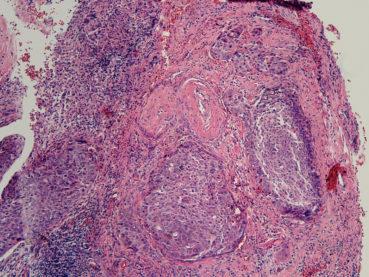

Rahim Ağzı Kanseri (Serviks Kanseri) nin Hücresel Tipleri Nelerdir? Aralarında Ne Fark Vardır? Rahim Ağzı Kanseri (Serviks Kanseri) nin Hücresel Tipleri Nelerdir? Aralarında Ne Fark Vardır? ...